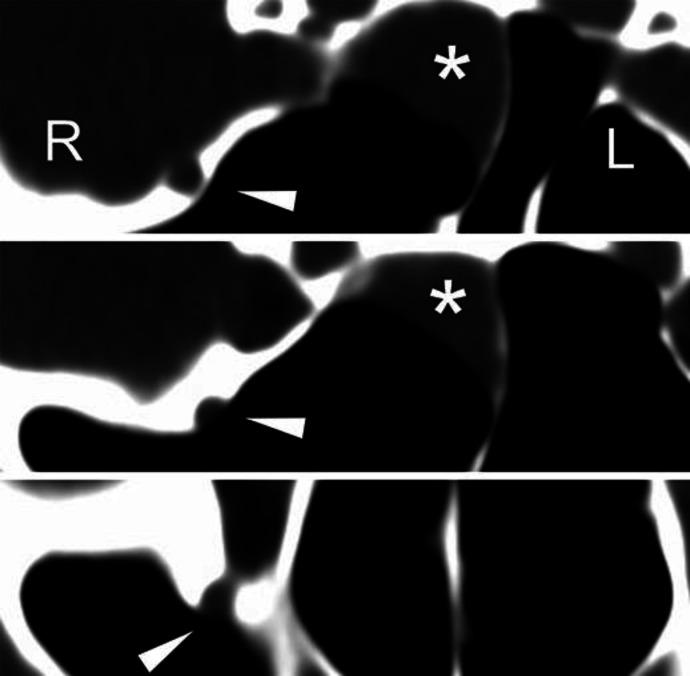

Although the etiology of classical trigeminal neuralgia is clearly understood to be neurovascular compression, the exact etiology of trigeminal neuralgia with continuous pain is often unknown. Mild sphenoid sinusitis is not usually considered to induce trigeminal neuralgia, especially when limited to the maxillary nerve. We report a rare case of trigeminal neuralgia of the maxillary nerve caused only by mild sphenoid sinusitis and discuss the significance of the anatomical structure and diagnostic procedures. A 45-year-old woman noticed a sudden onset of temporal pain followed by numbness on her right cheek. Her right gingiva also experienced sensory disturbance. The symptoms gradually subsided after the initial onset, but they persisted. She visited our hospital for further examinations and had no febrile episodes throughout the course. A tingling sensation and sensory disturbance were only identified in the maxillary nerve. No other neurological symptoms were noted. Magnetic resonance imaging revealed mild sphenoid sinusitis on the right side. The absence of the bony boundary between the sphenoid sinus and maxillary nerve was revealed using thin-sliced computed tomography (CT). The patient's symptoms were diagnosed as maxillary neuropathy caused by mild sinusitis. The bony defect around the maxillary nerve was considered to have affected development of the pathological process. Even mild sphenoid sinusitis can cause inflammation to spread to the maxillary nerve if no bony boundary exists between it and the sphenoid sinus. A coronal CT study is highly beneficial for clarifying the pathophysiological mechanism of trigeminal neuralgia limited to the maxillary nerve.

虽然经典三叉神经痛的病因被明确认为是神经血管压迫,但持续性疼痛性三叉神经痛的确切病因往往不明。轻度蝶窦炎通常不被认为会诱发三叉神经痛,尤其是当仅限于上颌神经时。我们报告一例仅由轻度蝶窦炎引起的上颌神经三叉神经痛罕见病例,并讨论其解剖结构和诊断程序的意义。一名45岁女性突然出现颞部疼痛,随后右侧脸颊麻木。她的右侧牙龈也出现感觉障碍。症状在初次发作后逐渐缓解,但仍持续存在。她到我院进一步检查,病程中无发热发作。仅在上颌神经中发现刺痛感和感觉障碍。未发现其他神经症状。磁共振成像显示右侧轻度蝶窦炎。使用薄层计算机断层扫描(CT)显示蝶窦与上颌神经之间无骨质边界。患者的症状被诊断为轻度鼻窦炎引起的上颌神经病变。上颌神经周围的骨质缺损被认为影响了病理过程的发展。如果蝶窦与上颌神经之间不存在骨质边界,即使是轻度蝶窦炎也可导致炎症蔓延至上颌神经。冠状位CT研究对于阐明仅限于上颌神经的三叉神经痛的病理生理机制非常有益。